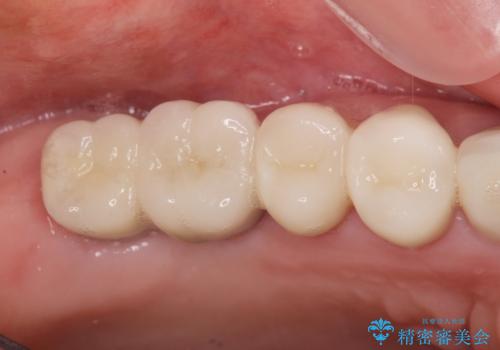

ブリッジのぐらつき インプラントを用いた奥歯の噛み合わせの再構築

- 数年前にいれた右上のブリッジが、「ぐらついて痛い、噛めない。」と改善を希望され来院されました。

X線写真より、咬合力負担能力に十分で無い親知らずを使用した長いブリッジが装着されており、力の負担に耐え切れずぐらつきが増加してきた状態です。

親知らず、ブリッジを抜去・撤去しインプラントを用いた咬合機能回復を行っていくこととしました。

しっかりと噛めるようになったと同時に歯ブラシもしやすくなり、食生活がまた楽しめるようになったと喜んでいただくことができました。